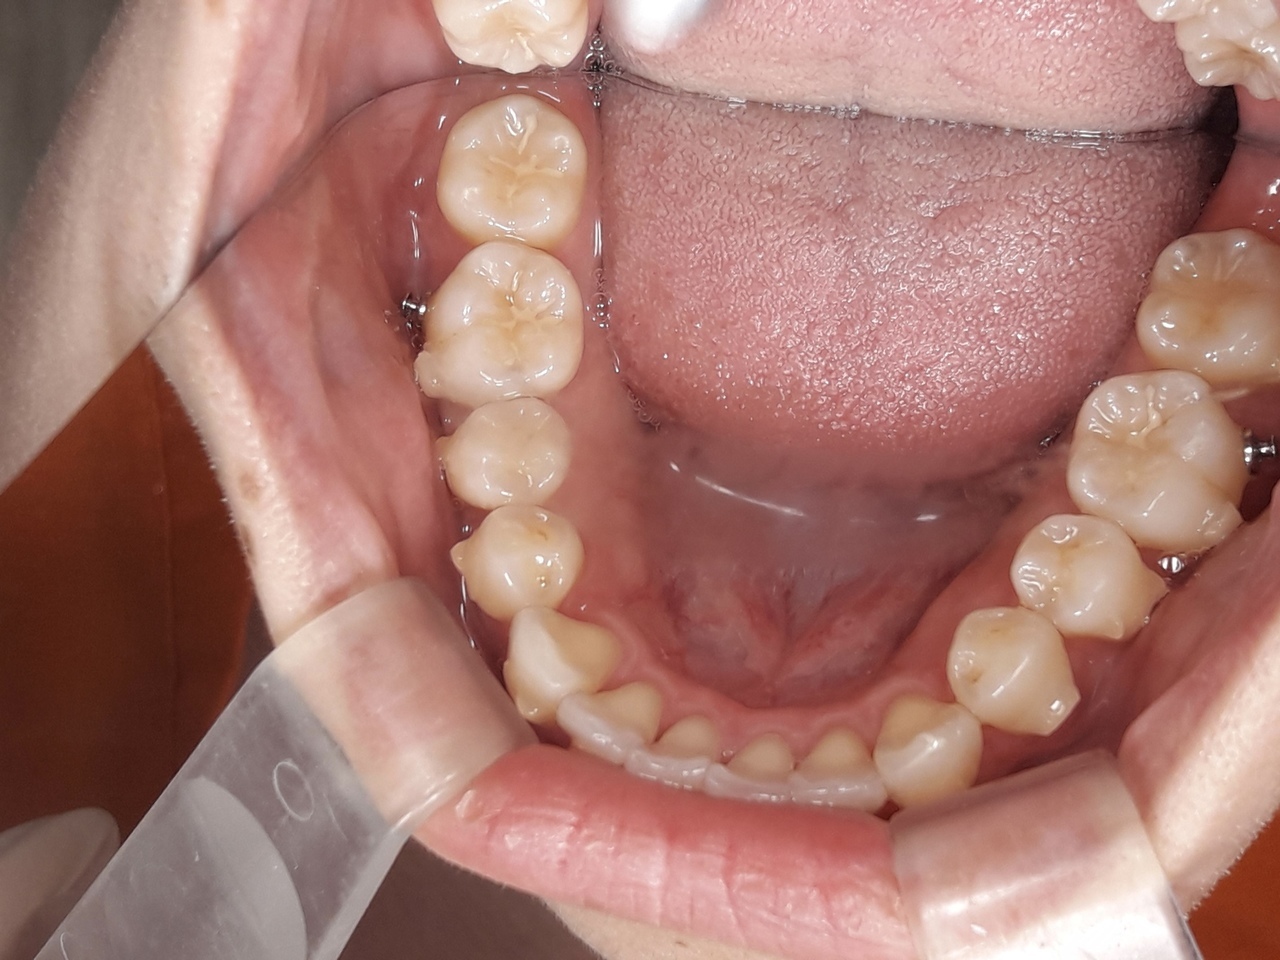

インビザを始めて4ヶ月が経ちました。

上の歯は、見た目の変化があまり分かりませんが、下の歯は前歯が徐々にまっすぐにならんできました!

インビザ開始4ヶ月